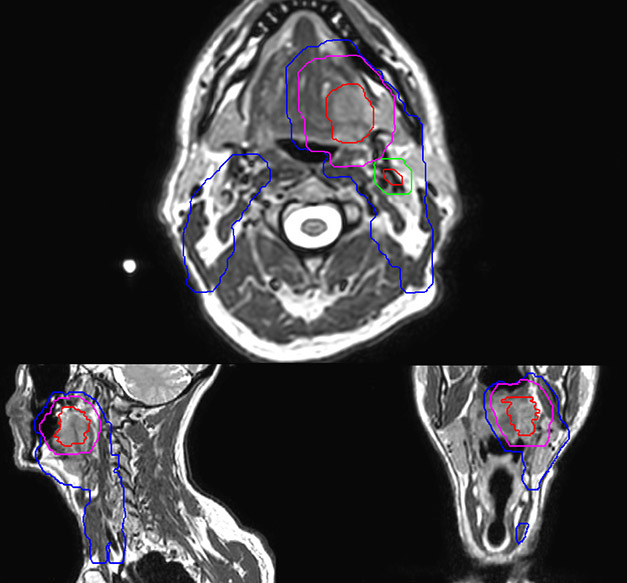

Epidermoid carcinoma of the left tongue base

The patient was diagnosed with an epidermoid carcinoma of the base of the left invading the amygdala lodge and the amygdaloglossal groove. Radiochemotherapy with curative aim was prescribed with a dose of 70 Gy for the tumor, 66 Gy on the suspicious nodes and 56 Gy on the elective drainage areas - in 33 fractions.

Simulation imaging

T2W 3D, 3D STIR and mDIXON MRI scans.

MR-based contouring and planning

MR-based target contouring on 3D T2W TSE in transversal, sagittal and coronal planes.

Personalized VMAT dose planned in Philips Pinnacle.